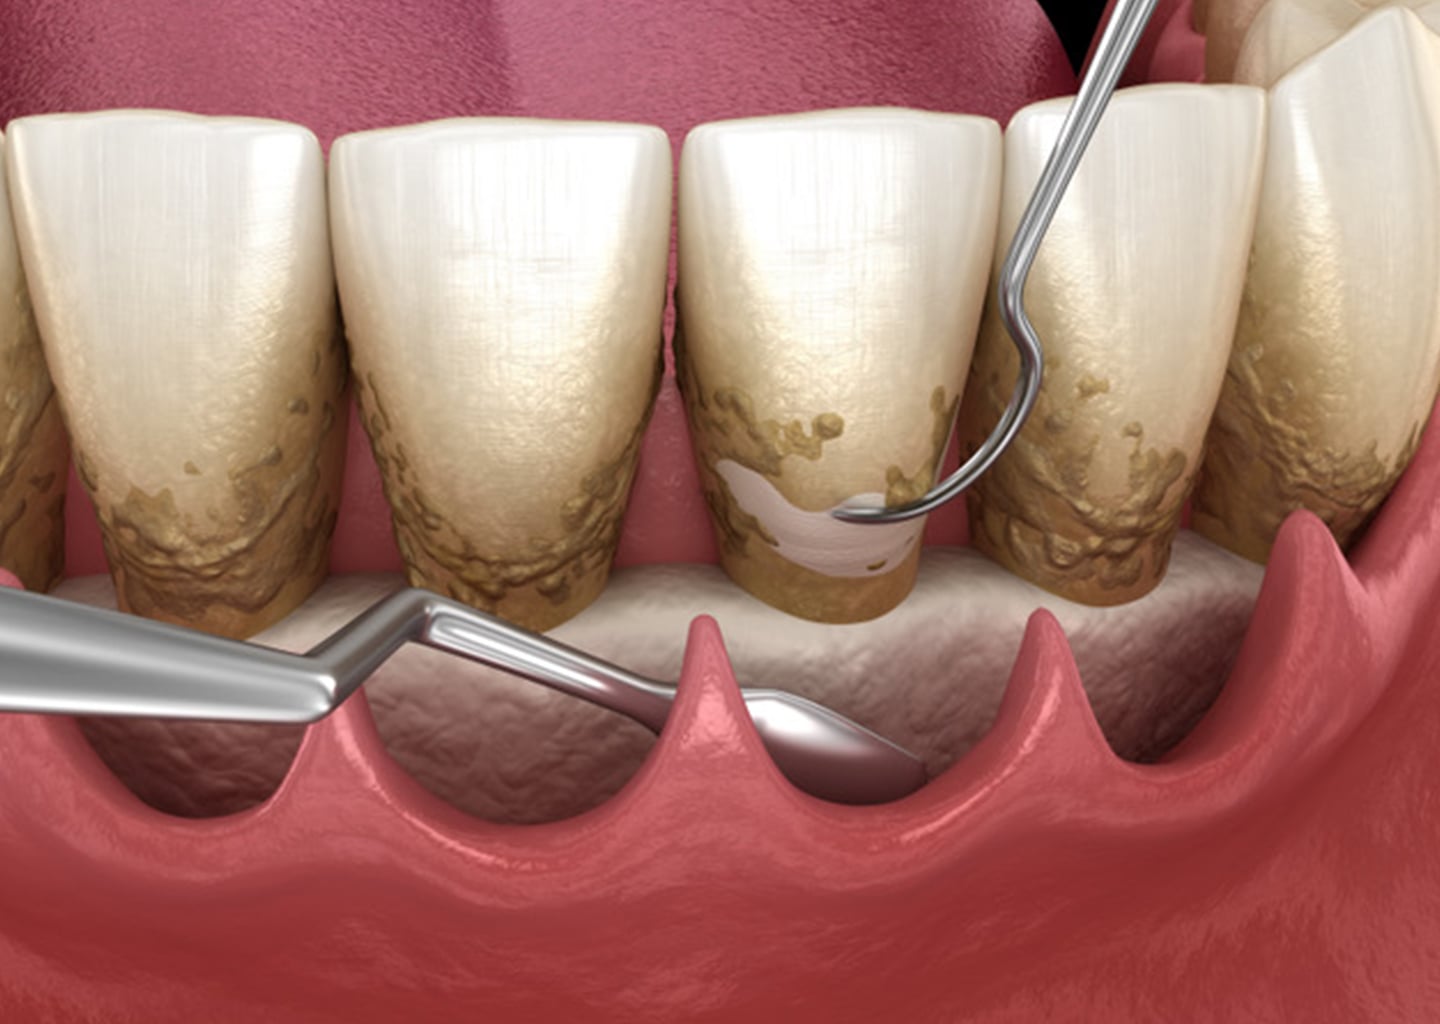

Zahnerhaltung

Unser Ziel ist es Ihre Zähne so lange wie möglich durch Prävention, Diagnostik und Therapie gesund und stark zu erhalten.